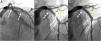

A 60-year-old man was admitted for unstable angina. Two-years ago he was treated with two bioresorbable vascular scaffolds (BVSs) on the proximal and distal segments of the left anterior descending coronary artery (Figure 1A, white arrows). Coronary angiography showed critical in-scaffold restenosis of the proximal BVS (Figure 1B, yellow arrow). Optical coherence tomography revealed heterogeneous tissue filling the BVS (Figure 2, A, B and D) with areas depicting bright neointimal hyperplasia with dorsal attenuation and marked shadowing of the underlying BVS struts. There was no evidence of scaffold disruption and neoatherosclerosis was considered the cause of late BVS failure. The patient was treated with a 3×15-mm sirolimus coated balloon catheter (drug-eluting balloon, DEB) (ratio of drug-eluting balloon to BVS size: 1:1) (MagicTouch™, Concept Medical Inc.) with excellent angiographic (Figure 1C) and optical coherence tomography (Figure 2, C and E) outcomes.